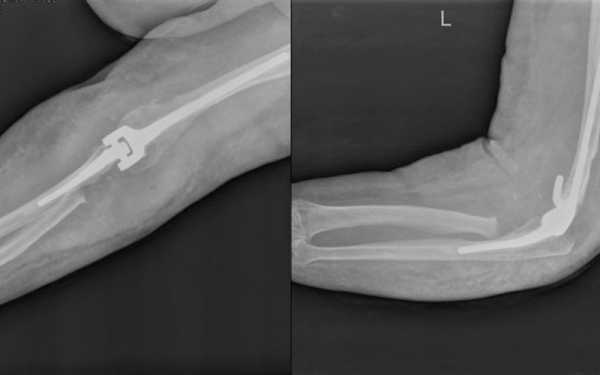

Восстановление целостности кости проводят с помощью особых приспособлений. Терапия заключается в стягивании тканей специальной проволочной петлей. Наличие осколков затрудняет процесс, так как приводит к укорачиванию поверхностей. В таких случаях накладывают компрессионные пластины. При особенно тяжелых травмах используют протезы — импланты, изготовленные из пластика и металла. Проверка успешности операции проводится рентгеновским снимком.

Суть хирургического лечения в полном вскрытии полости сустава, придании костным обломкам правильного положения и закреплении их в таком виде. Нередко применяется методика остеосинтеза, которая направлена на ускорение костного роста. При сильном повреждении головки лучевой кости может быть произведена замена эндопротезом. После того как операция сделана конечность фиксируют с помощью гипсовой лангетки.

После репозиции кости фиксируются с помощью штифтов, болтов или спиц. Иногда требуется сделать остеосинтез.

Осколки костей удаляются, а при необходимости и головка поврежденной кости. В этом случае ее заменяют эндопротезом.